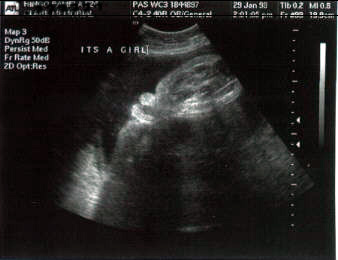

ثانيا : الولد

في الاسبوع ال19